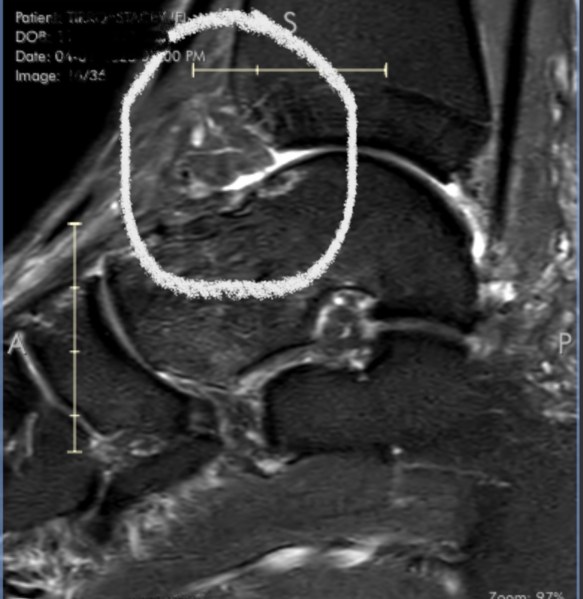

He opened up the images of the ankle and zoned in on the culprit.

At the front of the ankle joint, where the distal end of the tibia (the shin bone) meets the talus (the foot bone that connects to the tibia), there is some inflamed tissue that was invading the joint space. That is the reason why I felt pain and impingement whenever I flexed my foot and put weight into it. The bones kept hitting that soft tissue and couldn’t fully glide in it’s natural range of motion. The little white areas on the bone surface indicate some minor bone changes as a result.

Suddenly, everything made sense. Every time I took a long walking stride, stepped down from a higher level, or did a loaded calf stretch, it felt like something was getting in the way. That’s because there absolutely was something in the way.